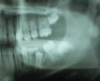

In 1998, a 7-year-old boy was brought in for emergency care with the chief complaint of toothache of the mandibular left permanent first molar. The malformed tooth was non-restorable and extracted, with no other treatment options. The child was not returned for continuing routine care but was returned on an emergency basis in 1999. He had a dentoalveolar abscess of the severely carious maxillary left permanent first molar, and the tooth was judged non-restorable (Figure 28). That molar was extracted. The patient was not returned to the office again until 4 years later, in 2003. The maxillary second molar had migrated into good position distal to the second premolar, and the third molar followed into place (Figure 29). The mandibular second molar was tipped mesially, followed by the crown of the third molar. Four years after that (2007), the patient returned as a 15-year-old. The second and third molars had migrated into position, with no orthodontic intervention (Figure 30).

Molar migrations after loss of first molars, 8-year history: 1999

Figure 28

Molar migrations after loss of first molars, 8-year history: 2003

Figure 29

Molar migrations after loss of first molars, 8-year history: 2007

Figure 30